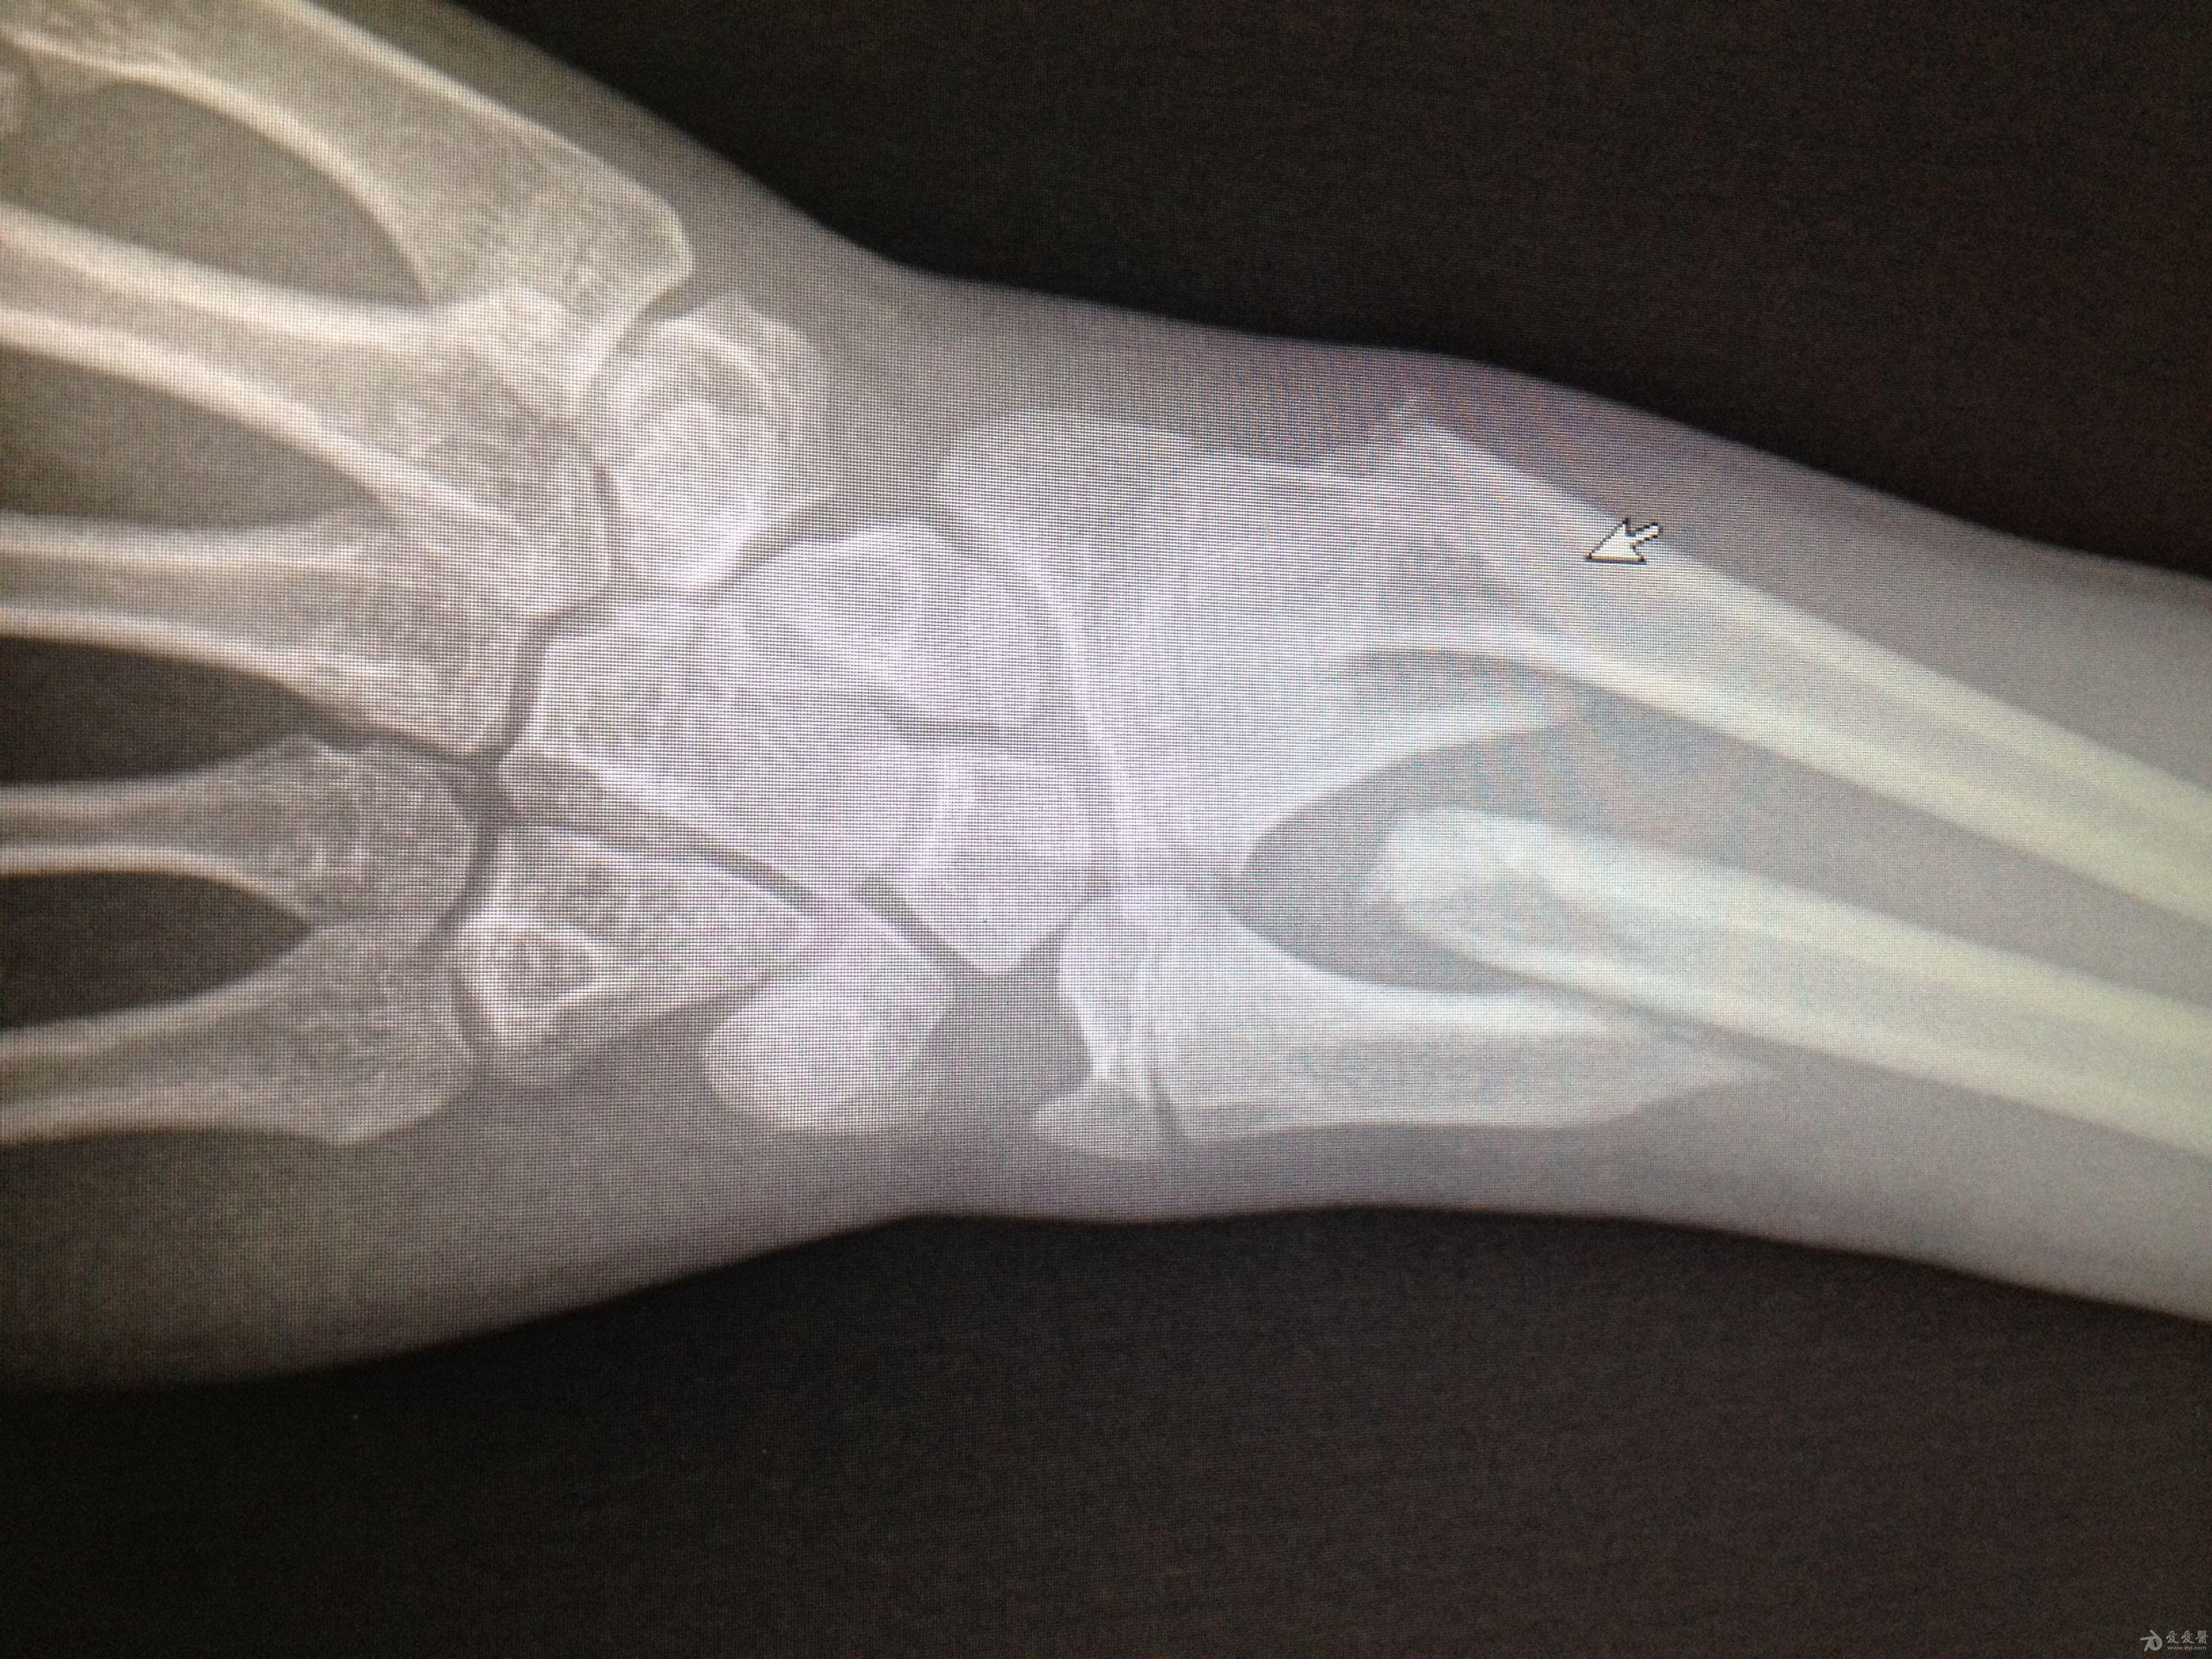

五岁男孩,摔伤后前臂双骨折,经外院两次手法复位后

前臂双骨折,手法整复交流 - 骨科与显微外科专业讨论